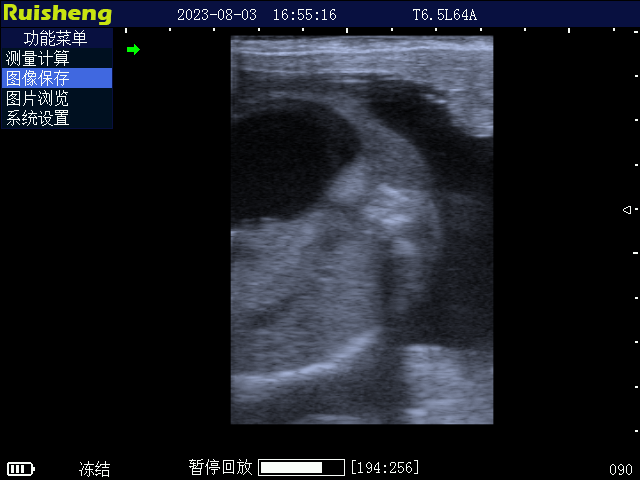

C8 牛用全数字B超诊断仪

• 【 畜牧业超声 】 C8 牛用全数字B超诊断仪 适用对象:[ 牛、羊、猪、马、骆驼、猫、狗 ]

产品介绍

8. 支持电子凸阵探头、直肠探头、微凸探头、高频线阵探头、羊用带把手专用探头、背膘探头